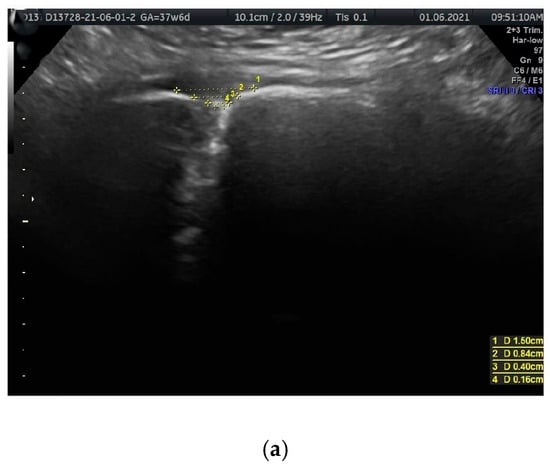

Ultrasound visualization was performed using coronal (frontal) planes, with the transducer directed from the superior margin to the inferior margin of the anterior pelvic bony wall, parallel to the anterior abdominal wall. In this plane, the PS resembles a funnel that gradually narrows inferiorly (Figure 1a,b and Figure 2a,b). The US scan consists of a wider, quadrangular part, which we propose to name the PS entry, and the proper, rectangular PS disc. The PS entry is bordered superiorly by the intertubercular line, which runs between the right and left PTs. The superior border of the PS disc forms the inferior border of this entry. The lateral borders, both right and left, are defined by lines connecting the PTs to the lateral-superior angles of the disc.

(a,b) The sonographic transducer was placed on the superior border of the anterior bony wall of the pelvis, parallel to the anterior abdominal wall. (a) Measured parameters displayed in the sonographic scan. Distance 1 = PT-PT (intertubercular distance); distance 3 = PSemw (PS entry middle width). (b) A corresponding schematic drawing exemplifying the measurements of PS parameters.